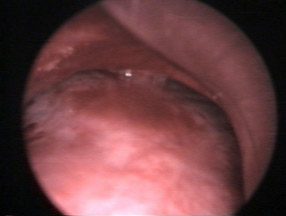

La microscopie confocale est une sorte de microscope qui permet de voir les cellules et l’architecture du poumon au cours d’une endoscopie et de façon totalement indolore. Elle a été obtenue par des fonds de recherche de l’INSERM et représente un outil très précieux de recherche.

La photo 2 vous montre la machine et la photo 3 une image obtenue.

Vous voyez par exemple ici le poumon d’un patient greffé pulmonaire : On retrouve le maillage régulier comme dans une ruche des alvéoles pulmonaires avec des cloisons très fines. Les cellules à l’intérieur (en blanc) qui font 10 à 15 microns sont des macrophages.